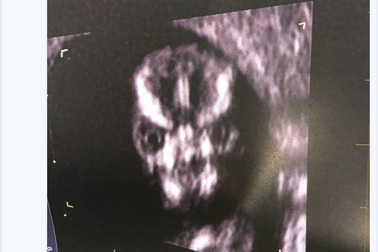

Thai nhi mang khuôn mặt như... chúa tể hắc ám hút hơn 32 nghìn lượt thích trên TwitterBà mẹ người Úc Sharni Turner tháng 9 vừa qua đã đi siêu âm và được phen hoảng hốt khi nhìn thấy hình ảnh siêu âm của con với khuôn mặt chính diện "xấu như quỷ".